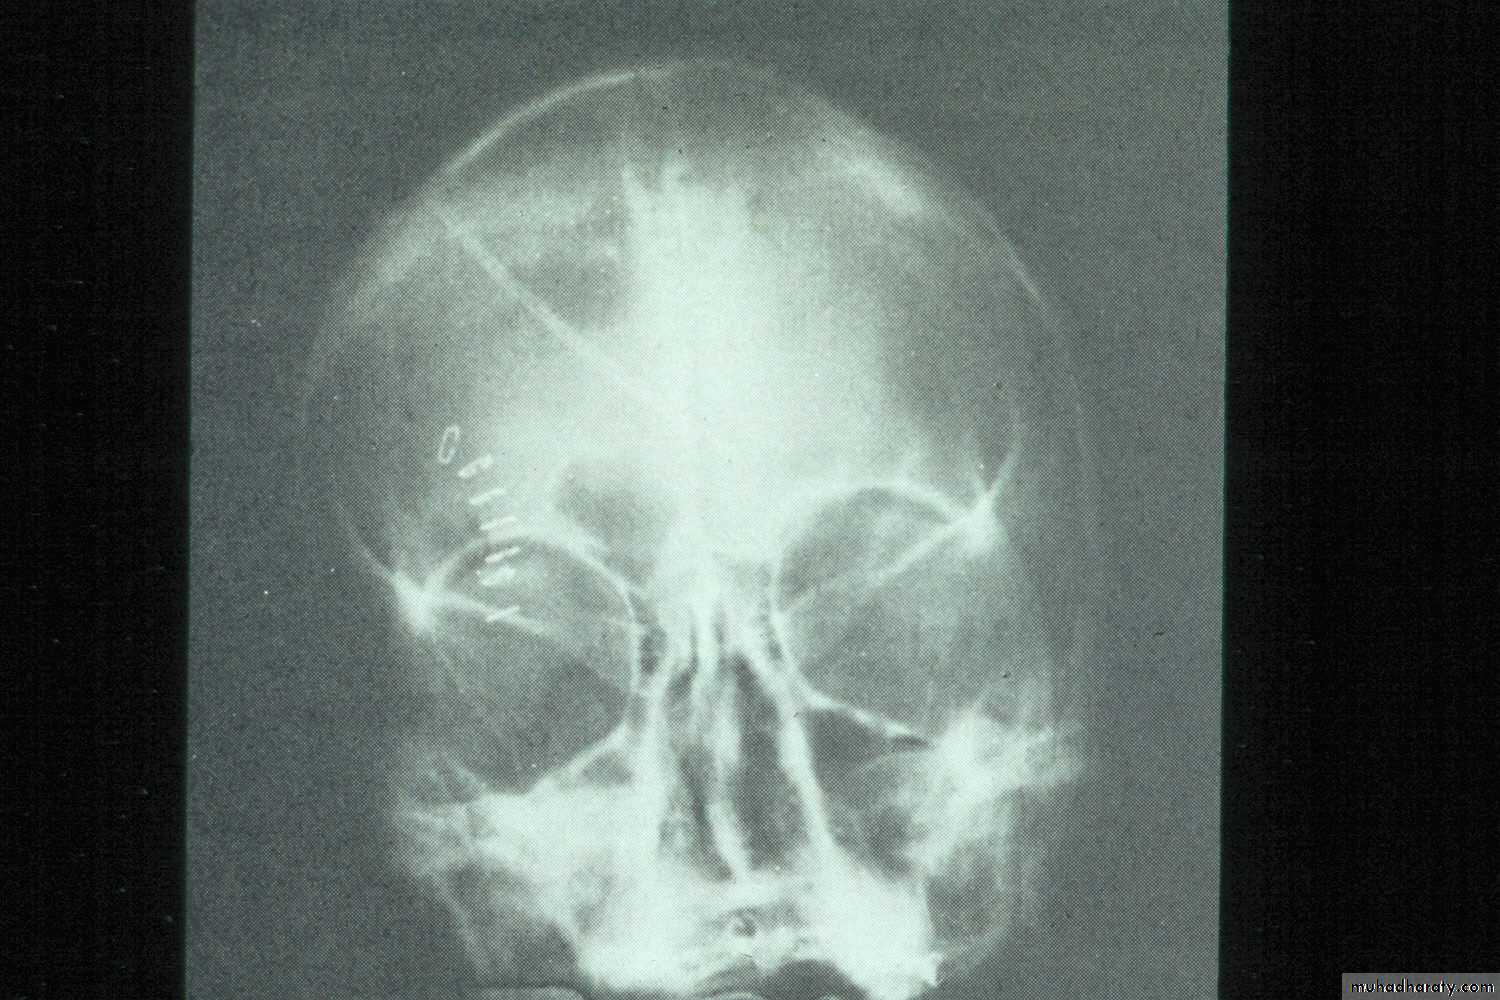

d. Occipitofrontal View: Is recommended to detect multisinusitis,

pansinusitis, if present.e. Tomography:This technique provides details of sinus structure.

Radiographic signs of sinus pathology :

Air fluid levels

Partial or complete opacification

Bony wall displacement

4 mm or more of mucosal wall thickening